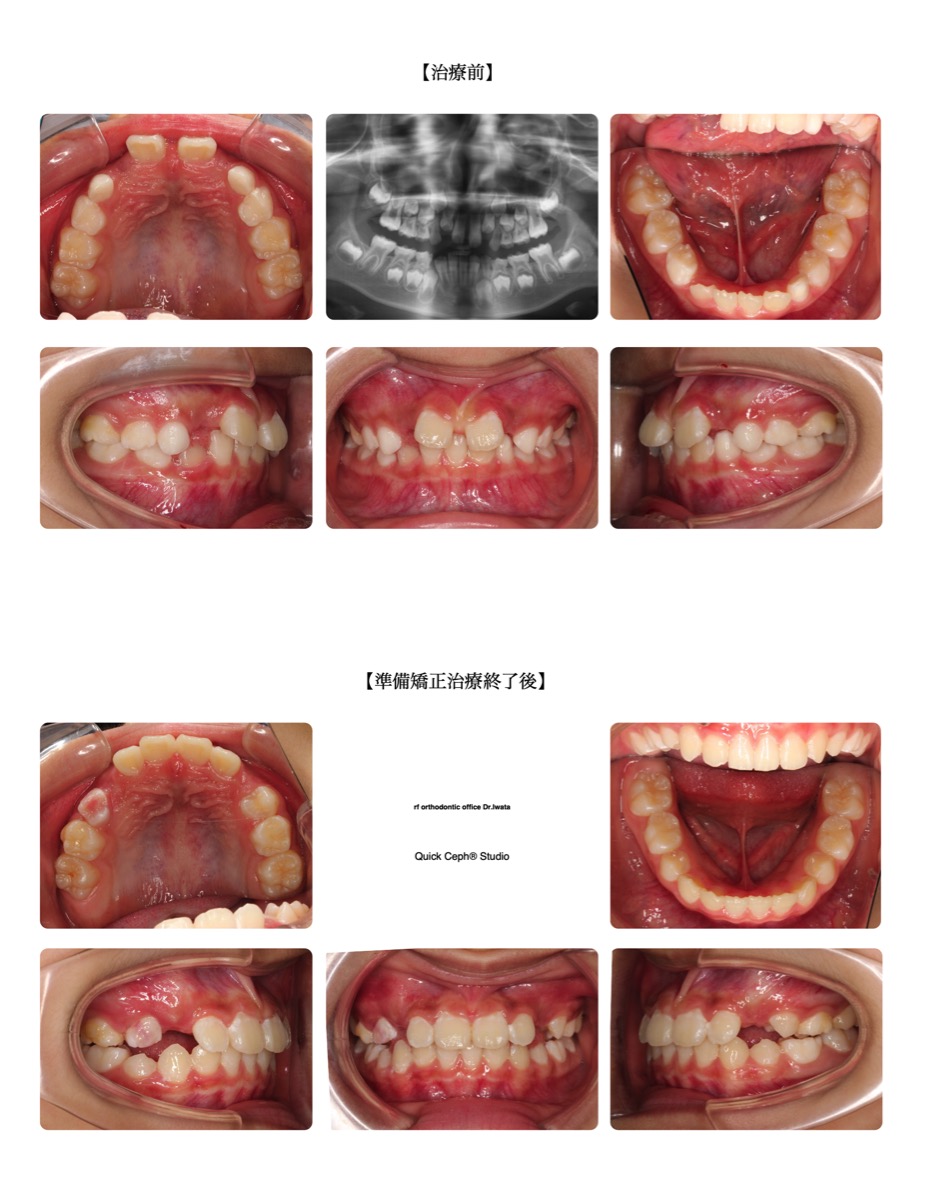

【主訴】上の前歯がハの字に開いている。下の前歯が上の歯茎に当たっている。

【主な症状】空隙歯列 過蓋咬合